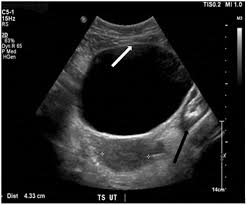

Echogenicity- Anechoic

echo free, its all black

air in lungs or fluid in bladder

Echogenicity- Hypoechoic

echo poor, dark grey

less dense soft tissue

Echogenicity- hyperechoic

echo rich, bright white

areas of increased density

in bone and metal